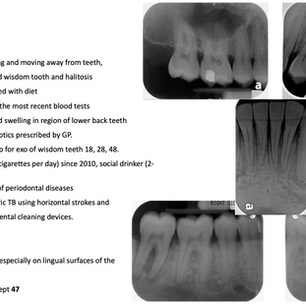

Clinical Presentation & Findings Discuss 1. Diagnosis & differential diagnosis From OPG, radiographic bone loss Greatest bone loss noted...

This article is made in courtesy of University of Sydney Dental School. Patient Case 1 OPG taken on 12/10/2020 Discuss 1. Calculate full...